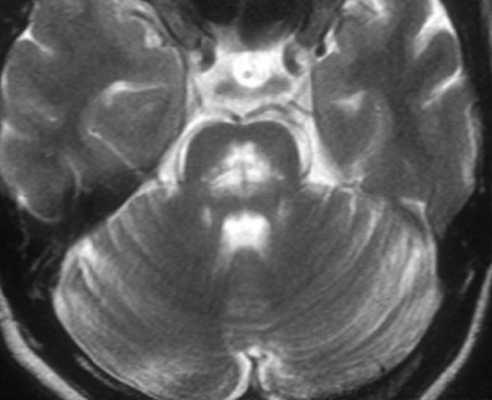

МРТ головного мозга выявляет скопление гемосидерина. Наиболее чувствительны градиентные Т2-взвешенные МРТ. Часто отмечается атрофия червя мозжечка, особенно, видимая хорошо на сагиттальных Т1-взвешенных МРТ.

МРТ головного мозга. Т2-взвешенная аксиальная МРТ через ствол. Тонкое темное кольцо гемосидерина вокруг ствола и в мозжечке. Сидероз головного мозга.

Для выявления поверхностного сидероза МРТ является методом выбора. Признаки весьма специфичные - мягкая мозговая оболочка и эпендимальная поверхность из-за скоплений гемосидерина имеют низкую интенсивность сигнала, особенно в области ствола мозга и мозжечка (червь и листки мозжечка - наилучшие места для выявления отложений). В давних случаях может наблюдаться атрофия мозжечка.

- Т2: снижение интенсивности;

- Т1: снижение интенсивности;

- Т2*: снижение интенсивности сигнала вплоть до его выпадения;

- SWI: снижение интенсивности сигнала вплоть до его выпадения;